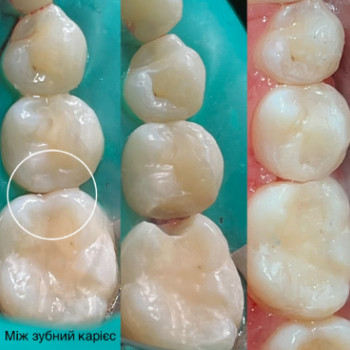

- Хочу рекомендувати дану стоматологію. Звернувся з болем у зубі. Лікування карієсу пройшло швидко та якісно. Рекомендую......

| Лечение кариеса | от 500 грн. / 60 мин. |